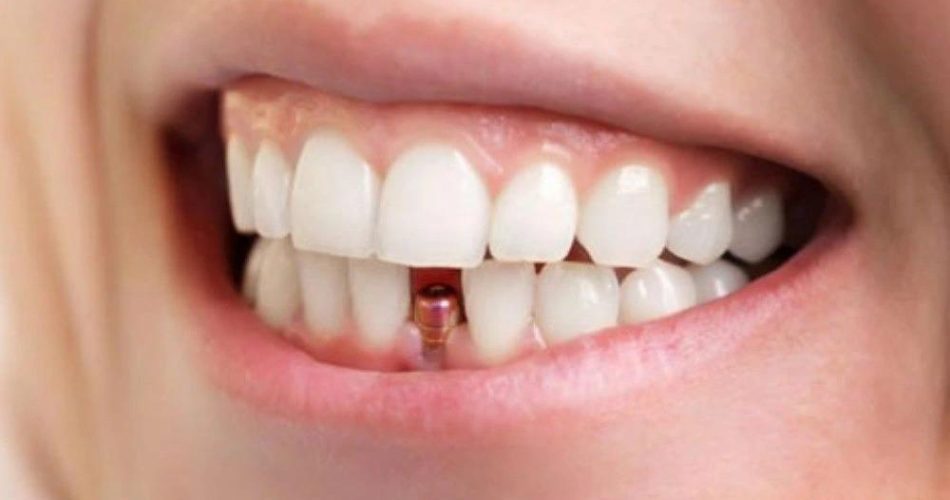

دندانپزشک با کمک دستگاههای پیشرفته، لثه من رو به طور دقیق برش داد. بعد از اون، پایه ایمپلنت که ظاهرش شبیه به پیچ هست رو داخل استخوان فک قرار داد.

برای این که تاج موقت روی پایه قرار بگیره، با کمک نرمافزار، قالبی از دندانهای من ساخته شد و یک تاج سفید موقت روی ایمپلنت قرار گرفت. برام عجیب بود که بلافاصله بعد از جراحی، دندان جدیدم رو ببینم. البته این تاج موقته و بعد از دوره نقاهت، باید تاج دائمی جایگزین اون بشه.

در طول این مدت، تنها چیزی که احساس کردم، یه فشار سبک موقع قراردادن ایمپلنت بود. اون روز عصر، با وجود بیحسی، هم میتونستم لبخند بزنم و هم غذا بخورم. بعد از ۶ ماه، ایمپلنت دندان من دائمی شد و الان کاملا شبیه به دندانهای طبیعی شده.

اگر از ایمپلنت معمولی استفاده کنید، حداقل ۳ ماه طول میکشه تا زیبایی و قدرت جویدن موادغذایی رو به دست بیارید؛ اما اگر ایمپلنت فوری رو انتخاب کنید، با دندان موقت از کلینیک بیرون میرید که زییایی طبیعی خیرهکنندهای داره.